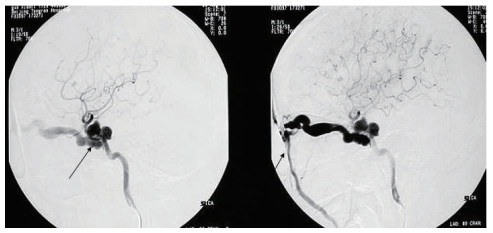

患者入院后行全脑血管造影明确诊断,见图 3。结果显示118例(81.82%)瘘口位置位于颈内动脉C4-C5段,26例(18.06%)位于C3-C4段。引流方向135例(94.75%)向眼上静脉、岩下窦引流。确诊CCF后患者行Matas试验,后在颈内动脉海绵窦瘘栓塞术中,瘘口未见进一步扩大,海绵窦无进一步扩张。144例患者中可脱球囊是最常用的栓塞材料[9],占120例(83.88%),弹簧圈9例(6.25%),弹簧圈+Onyx胶12例(8.33%),Willis覆膜支架3例(2.08%)。

| 图 3 黑色箭头显示了异常增粗的眼静脉 Fig 3 Black arrows show abnormally thickened ocular veins |